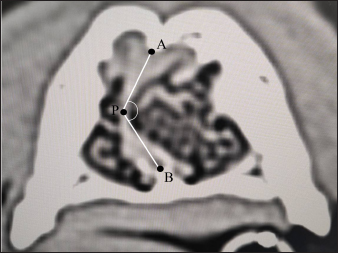

where length of the facial skull (LF) is the length between the nasion and the cranial edge of the olfactory bulb horizontal to the hard plate and cranial length (CL) is the length between the cranial edge of the olfactory bulb and inion horizontal to the hard plate (Fig. 3).

Fig. 3. CT measurements for Sct-Index (sagittal section). LF: the length between the nasion and the cranial edge of the olfactory bulb horizontal to the hard plate. CL: the length between the cranial edge of the olfactory bulb and the inion horizontal to the hard plate. Window width: 5,000, window level: 1,000.